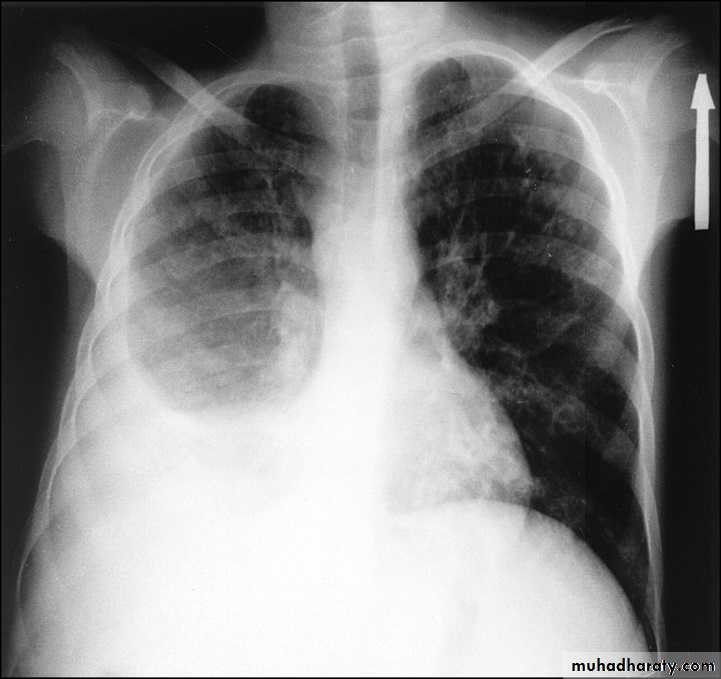

PneumothoraxPneumothorax refers to the presence of gas (air) in the pleural space. When this collection of gas is constantly enlarging with resulting compression of mediastinal structures it can be life-threatening and is known as a tension pneumothorax

A pneumothorax is, when looked for, usually relatively easily appreciated. Typically they demonstrate:

visible visceral pleural edge see as a very thin, sharp white line

no lung markings are seen peripheral to this line

the peripheral space is radiolucent compared to adjacent lung

the lung may completely collapse

the mediastinum should not shift away from the pneumothorax unless a tension pneumothorax is present

A tension pneumothorax

A tension pneumothorax occurs when intrapleural air accumulates progressively in such a way as to exert positive pressure on mediastinal and intrathoracic structures. It is a life threatening occurrence requiring rapid recognition and treatment is required if cardiorespiratory arrest is to be avoided.Radiographic features

A pneumothorax will have the same features as a run-of-the-mill pneumothorax with a number of additional features, helpful in identifying tension. These additional signs indicate over expansion of the hemithorax:

ipsilateral increased intercostal spaces

shift of the mediastinum to the contralateral side

depression of the HYPERLINK "http://radiopaedia.org/articles/diaphragm" hemidiaphragm